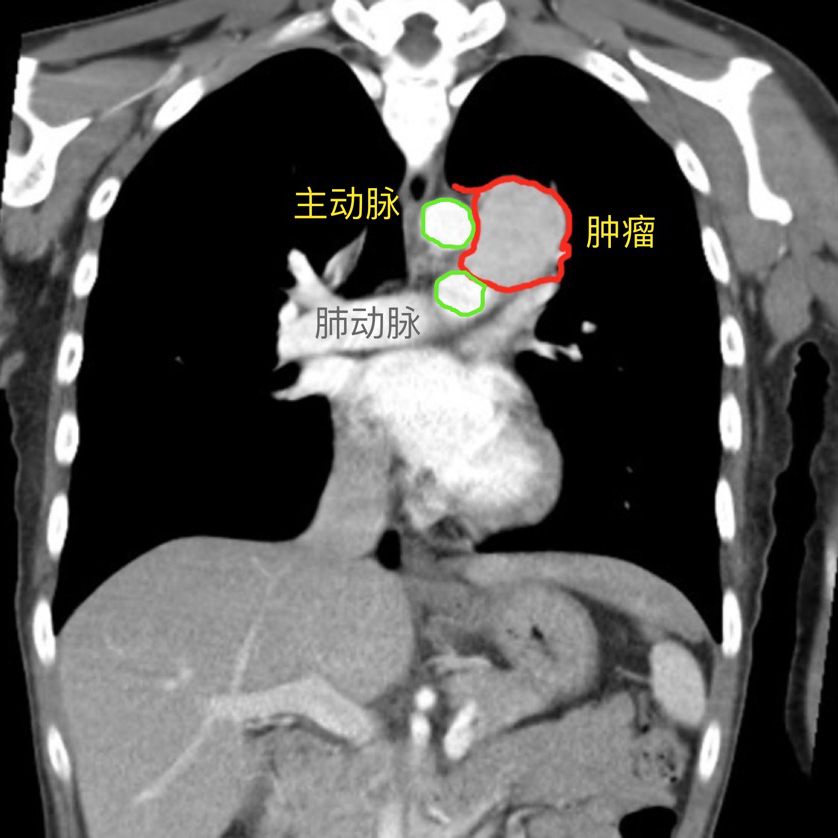

12月23日,主刀医生李力向全科汇报了第二日手术计划,全科对手术方案进行讨论。肿瘤位于主肺动脉窗,最大径接近15厘米,与膈神经、左侧喉返神经、主动脉、肺动脉均关系密切,手术风险高。全科讨论进一步完善了手术方案和应急预案。

图3:术前CT可见,肿瘤位于主肺动脉窗,与膈神经、左侧喉返神经、主动脉、肺动脉关系密切;图4:手术切除的标本,最大直径接近15cm,胸外科供图